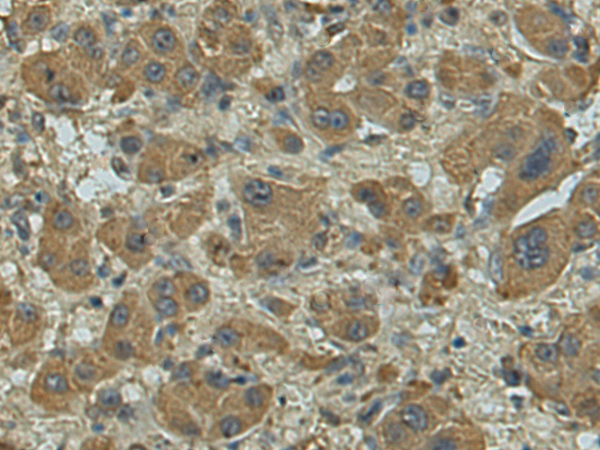

分类: 科研抗体货号: P10049别名: C1orf83应用: IHC反应种属: Human, Mouse, Rat